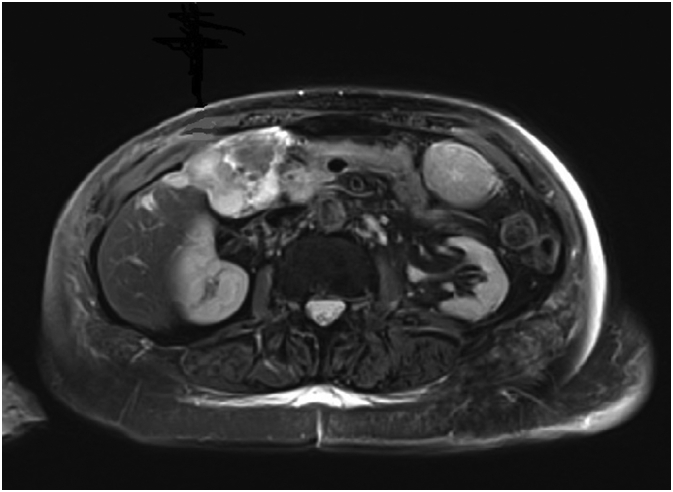

The latter showed a well-differentiated adenocarcinoma. We completed the pre-operative staging with a hepatic magnetic resonance that showed also a suspected malignancy of gallbladder with invasion of cystic duct and CBD (Fig. 3).